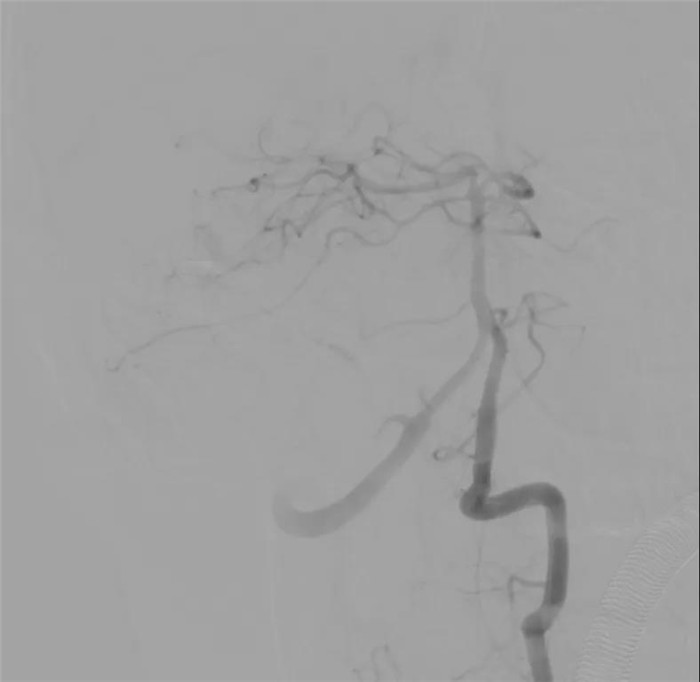

“我建议尝试通过最后这支供血动脉争取完全栓塞,开颅只做血肿清除,尽量减少对脑干的影像。”陈晓霖说,大家随后对最后一支供血动脉发起“进攻”。通过不断调整微导丝的形态,将微导管超选到尽可能靠近畸形巢的位置,王明泽向微导管内推入栓塞剂。随着一团栓塞剂慢慢出现在引流静脉与病灶交界的位置,畸形完全被栓塞,经过造影复查,原本“一团乱麻”的病灶区域十分干净,只有几团栓塞剂的痕迹若隐若现,小脑的各个分支动脉都被完好保留!

手术间内士气大振,医护人员相互配合,开颅、枕骨大孔减压,陈晓霖在显微镜下对患者小脑和第四脑室内血肿进行清除,并对血肿壁上疑似的异常血管进行电凝。

经过复查,小豪的动静脉畸形被完全消灭,正月初三0时30分许,手术结束,用时9小时30分。